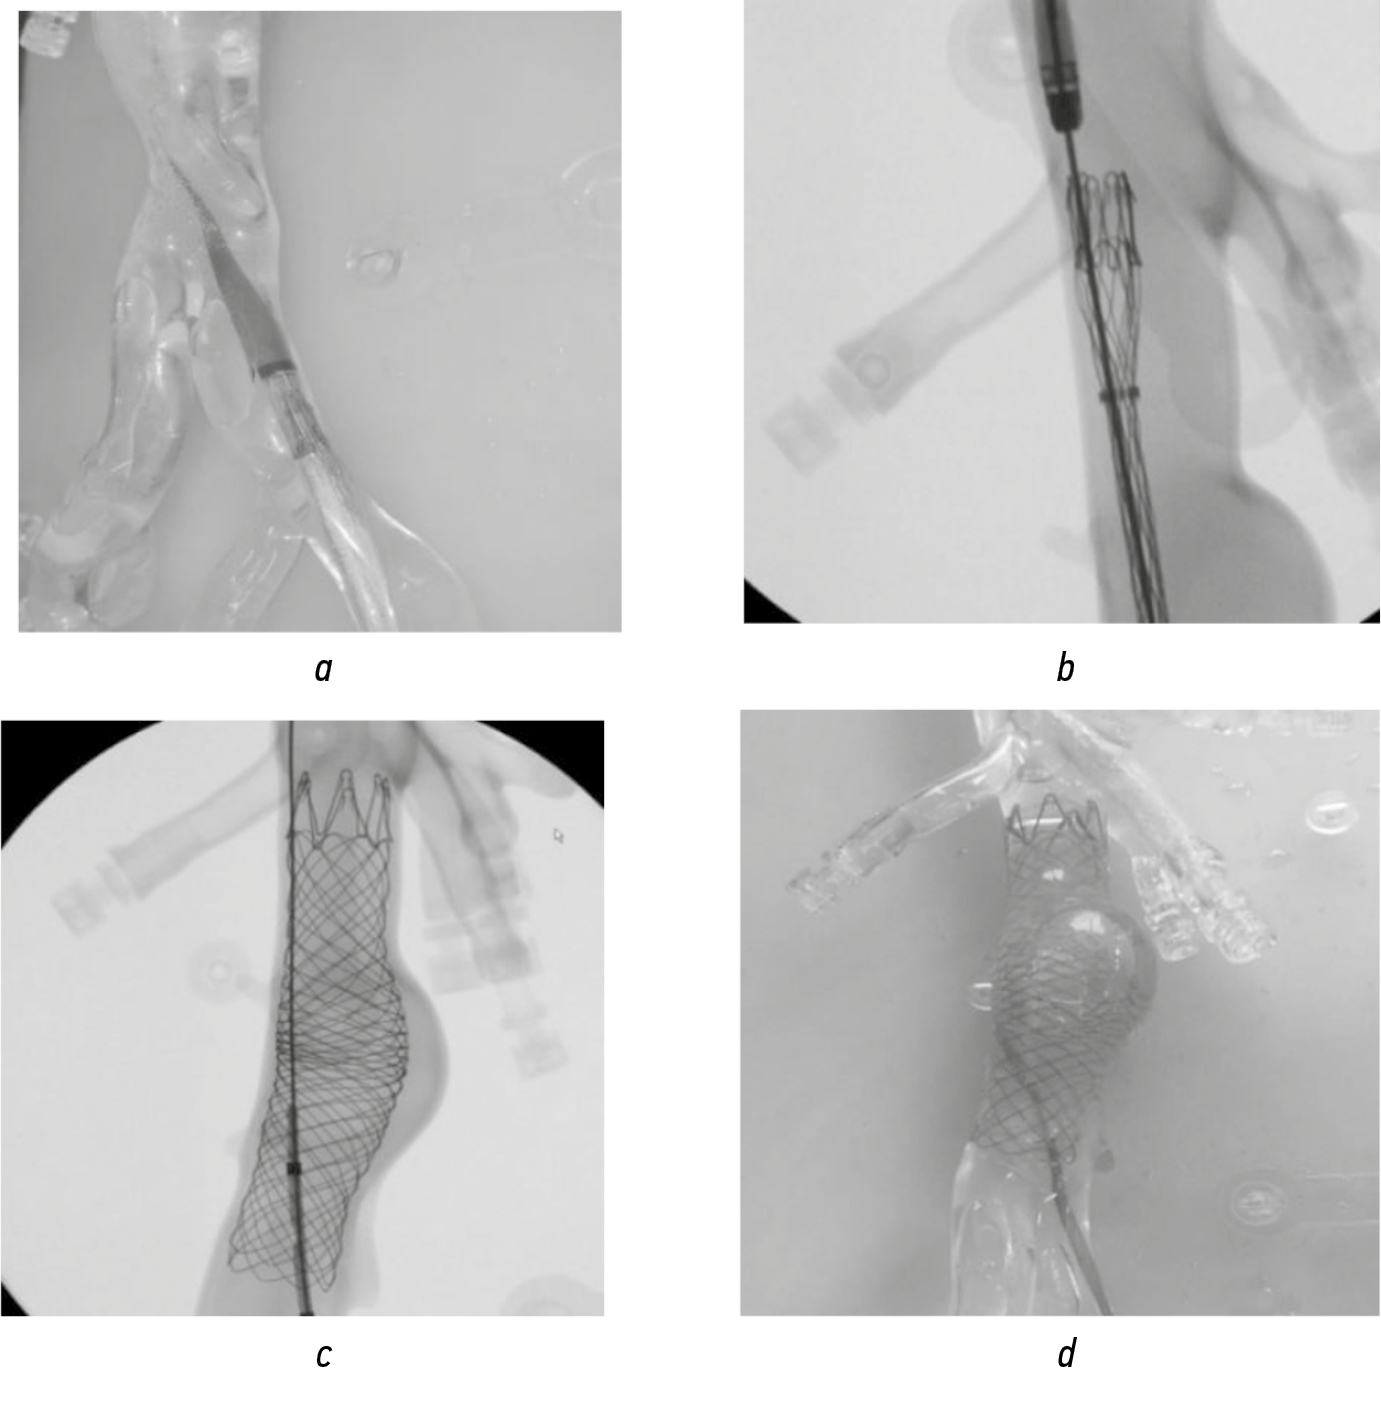

Fig. 11. Stages of stent graft implantation: а — the stent graft in the delivery system is inserted into the abdominal aorta model; b — the system is positioned below the mouths of the renal arteries (model); c — the stent graft is implanted in the aneurysm zone; d — appearance of the product implanted in the silicone model of the abdominal aneurysm aorta

By using a Phillips Veradius mobile angiographic unit, the process of endoprosthesis replacement of the abdominal aorta was simulated. A stent graft was implanted along a super-rigid guidewire passed through the iliac artery into the abdominal aorta, which was positioned and installed in the zone of simulated dilatation so that the upper border of the structure was at the level of the renal arteries. Omnipaque enable control. After installation, the stent was post-dilated with a large-diameter balloon (Fig. 11).

Testing using a phantom (demonstration of the stages of product implantation). Aneurysmal dilatation with and without dissection was simulated on a silicone aortic phantom (Fig. 9).

The contour of the silicone aortic phantom was filled with a blood replacement solution that simulated the rheological properties of native blood. A perfusion pump was used to create pulsatile blood flow with a maximum pressure of 200 mm Hg (Fig. 10).